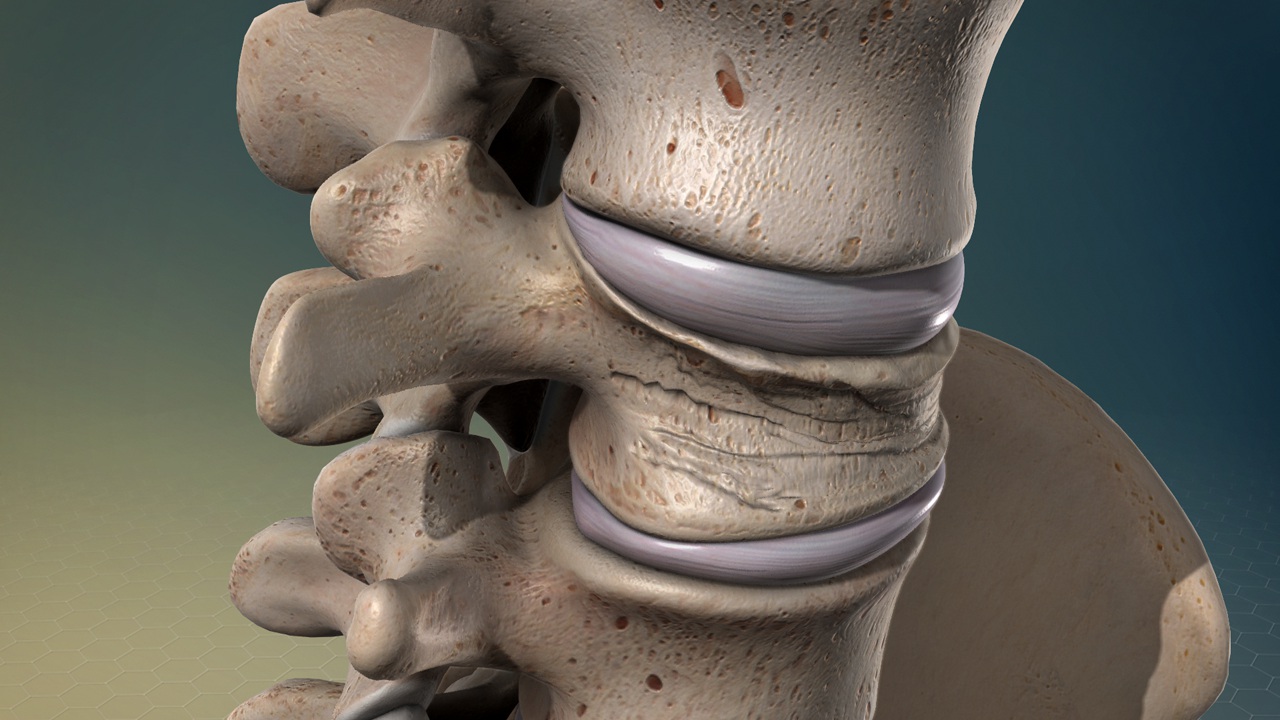

Рентгеновские снимки и медицинские изображения компрессионных переломов